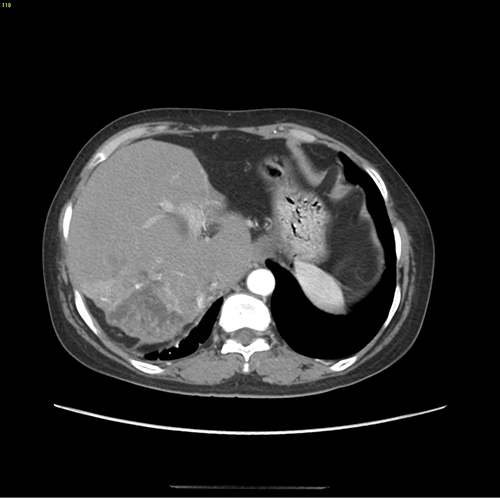

右肝后叶、左肝外侧叶胆管结石并肝萎缩、中肝肥大---右肝后叶、左肝外侧叶切除、胆囊切除